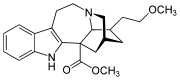

Indoles

- 18-Methoxycoronaridine

- 7-Acetoxymitragynine

- 7-Hydroxymitragynine

- ψ-Akuammigine

- Akuammidine

- Akuammine

- Coronaridine

- Eseroline

- Hodgkinsine

- Ibogaine

- Mitragynine

- Mitragynine pseudoindoxyl

- Noribogaine

- Pericine

- Pseudoakuammigine

Structures

| Indoles | ||||

|---|---|---|---|---|

|

7-Acetoxymitragynine |

|

Akuammidine |

|

|

|

-Mitragynine_Structural_Formula_V1.svg.png.webp)

|

|

|